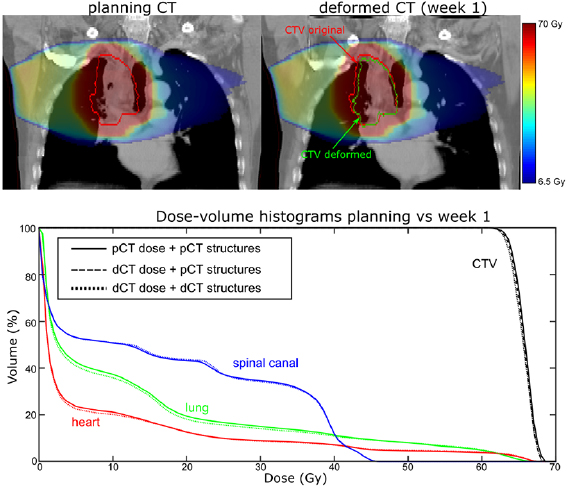

To demonstrate the clinical application of the DIR method, we performed serial dose calculations on CBCT anatomy on Patient 5, a subject that appeared to demonstrate a steady decrease in tumour size over the course of four weeks. As there were no obvious sudden changes in tumour size from one week to the next it was not clear from visual assessment at what time point a replan might be appropriate.

The CTV data suggests there was a reduction in target coverage early on in the treatment with V99% for the original CTV structure dropping from 96.2% to 92.7% in Week 1. Dose distributions as calculated on the pCT and the Week 1 dCT are shown at figure 10.

Figure 10. (Top) dose distributions calculated on the pCT and week 1 dCT and (bottom) dCT DVHs overlaid with the pCT DVHs.

Download figure:

Standard image High-resolution imageA reduction in GTV size is evident on visual inspection of the two images. As a result, the proportion of soft tissue present within the original CTV volume was less on the Week 1 dCT image than on the pCT image. As soft tissue absorbs dose to a greater extent than lung tissue, V99% coverage of the original CTV structure was correspondingly reduced. Unlike the original CTV structure, the deformed CTV reflected the reduction in GTV size, which meant that V99% coverage for this structure only reduced to 94.8%.

While these results demonstrate the type of quantitative information that may be derived from our method, it is important to note that neither the original, nor deformed, CTV is representative of the actual clinical CTV at that point in time and they should not be relied on as such. What these structures can do, however, is provide information to the clinician to assist in the outlining of an appropriate CTV for dose evaluation. This is discussed further in the section below.

Due to the proximity of the target volume to the spinal canal there was a clear risk that anatomical change would cause this volume to breach the clinical tolerance (47 Gy < 0.1 cc). Table 4 includes data for both the spinal canal and the spinal canal PRV structure (spinal canal + 5 mm) which suggests that, while the PRV structure breached tolerance in both Week 2 (Dmax = 57.1 Gy) and Week 3 (Dmax = 58.8 Gy), the spinal canal volume itself remained well within tolerance. This information would prove useful to the clinician in deciding if a replan is necessary. Other OAR structures remained well below tolerance (Lung V20 < 30%, Heart V40 < 30%).